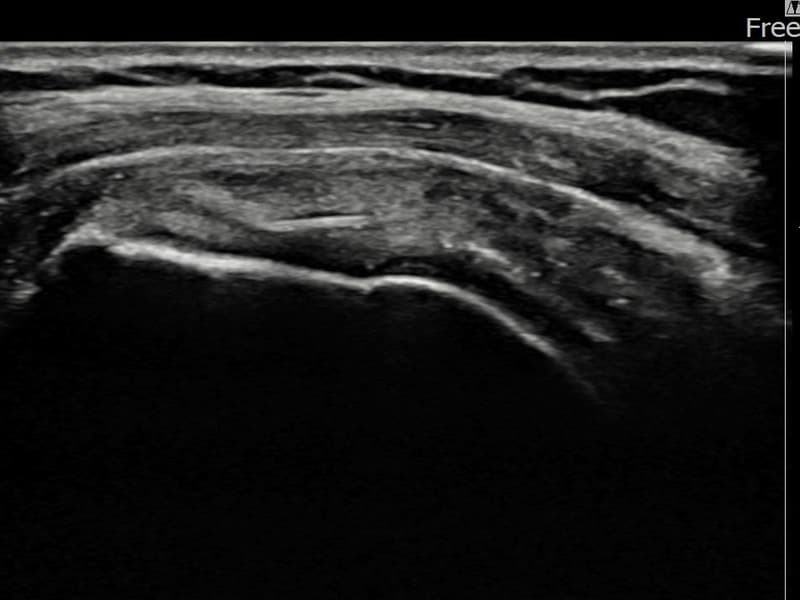

术后

术前超声确认左侧 冈上肌腱 附着部部分撕裂,左侧冈上肌腱回声不连续伴肌腱缺损(5mm × 3mm (肌腱厚度约25%缺损))。术后超声显示撕裂部位充满再生组织,肌腱连续性恢复,回声模式正常化。